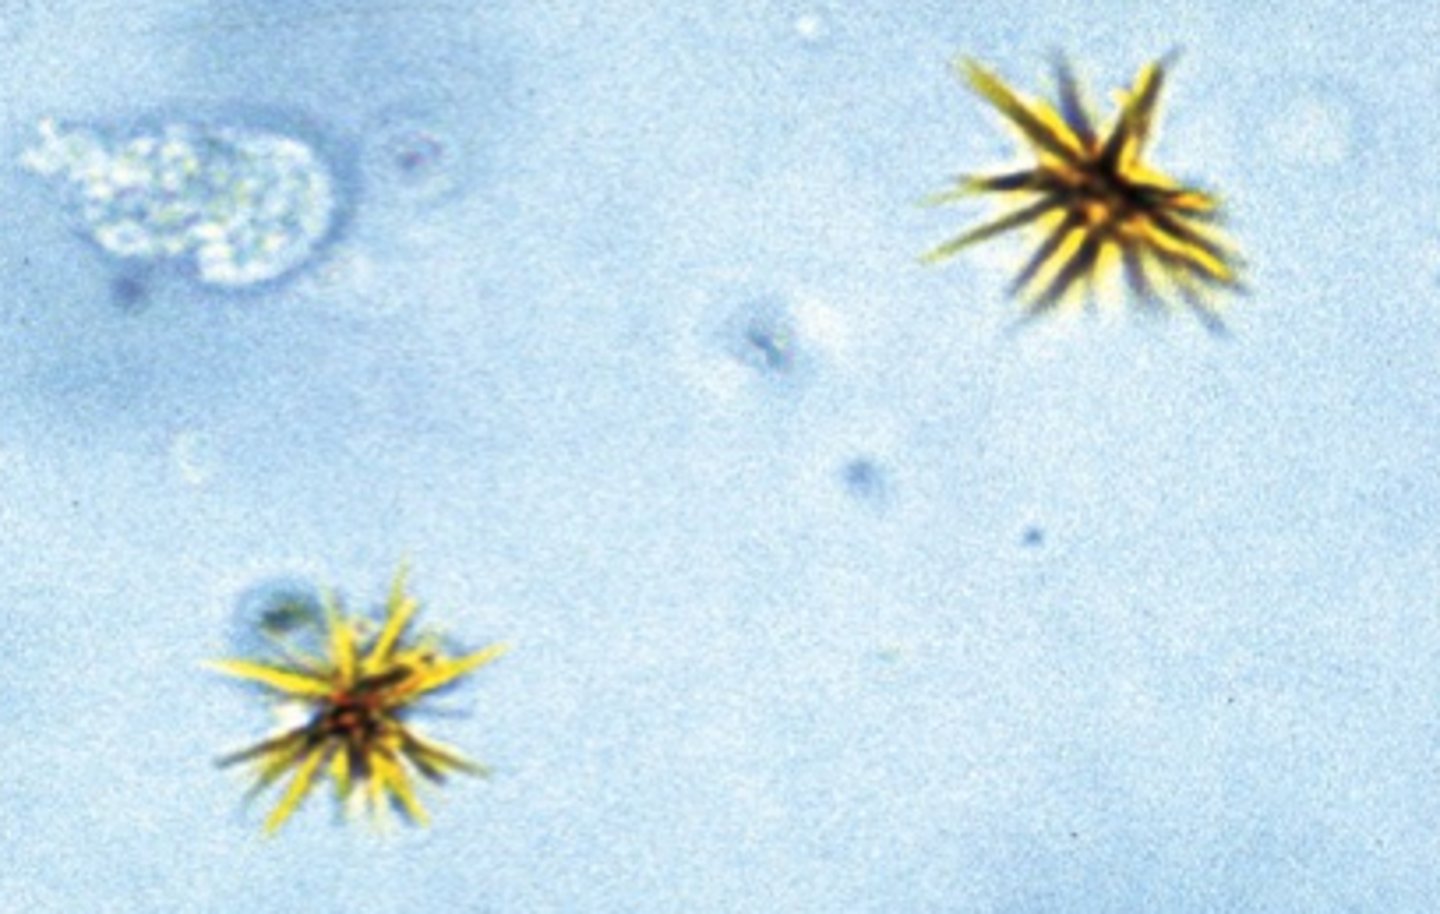

ammonium (bi)urate crystal

urine

round, golden brown in color with irregular spicules